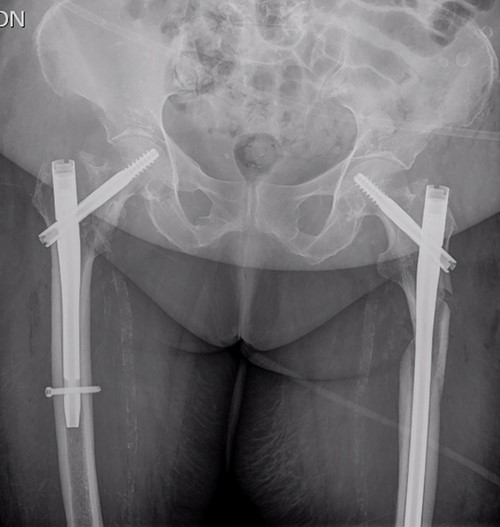

On examination, external rotation deformity of both lower limbs was evident, as well as pain upon palpation in the trochanteric region and during mobilization. The radiological study revealed a left and a right intertrochanteric femur fracture (Fig. 1). She was given analgesia, immobilized with two cutaneous tractions (Fig. 2), and was admitted to the Orthogeriatric Unit.

Patient immobilization in the emergency department: each lower limb was temporarily immobilized with a 3-kg skin traction.